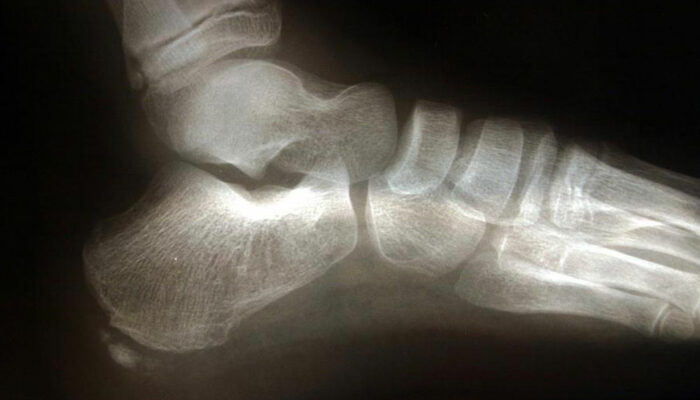

Commonly affecting athletes who frequent activities include running and jumping, heel spur is caused due to calcium deposits on the underside of the heel bone. The symptoms include inflammation of tissues and tendons near the spur, pain while walking or jogging, formation of calluses, swelling or redness of the affected part of the heel.